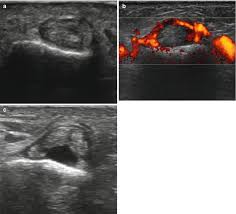

Imaging Of Rock Climbing Injuries Radiology Key

Imaging Of Rock Climbing Injuries Radiology Key from radiologykey.com

There are 2 musculotendinous units that could be involved, the flexor digitorum superficialis (fds) and flexor digitorum profundus (fdp). The moment arm of the fdp tendon over the pip joint has thus increased by 3 per cent. Surgery is often necessary to repair complete tendon tears. Five flexor tendon zones were described based on anatomy that help dictate treatment principles ( fig. Flexor tendon pulley injuries in rock climbers closed pulley ruptures are rare in the general population but occur more frequently in rock climbers due to biomechanical demands on the hand.